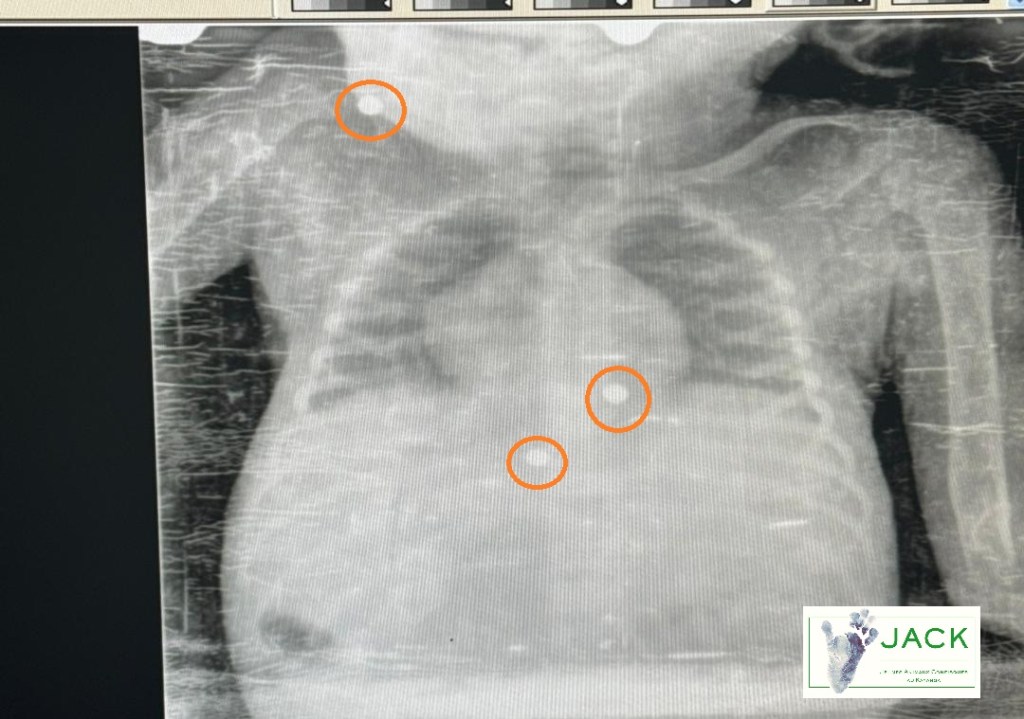

En mars 2024, des radiographies avaient révélé une réalité déchirante : trois balles étaient logées dans le corps de Kindu, vestiges douloureux de son passé.

Le vétérinaire de J.A.C.K., Dr Calvin, a pu en extraire une, mais la localisation exacte des deux autres et la possibilité de les extraire restaient un mystère.

Les résultats confirment la présence d’une balle qui se déplace dans son corps et d’une autre légèrement encastrée dans la colonne vertébrale. Madame Roxane, notre fondatrice, attend l’avis de divers spécialistes afin de déterminer si une intervention chirurgicale est possible ou si ces fragments devront être surveillés à long terme. Ces décisions seront cruciales pour son avenir, notamment en vue d’une réintroduction dans la forêt, symbole de sa liberté retrouvée.